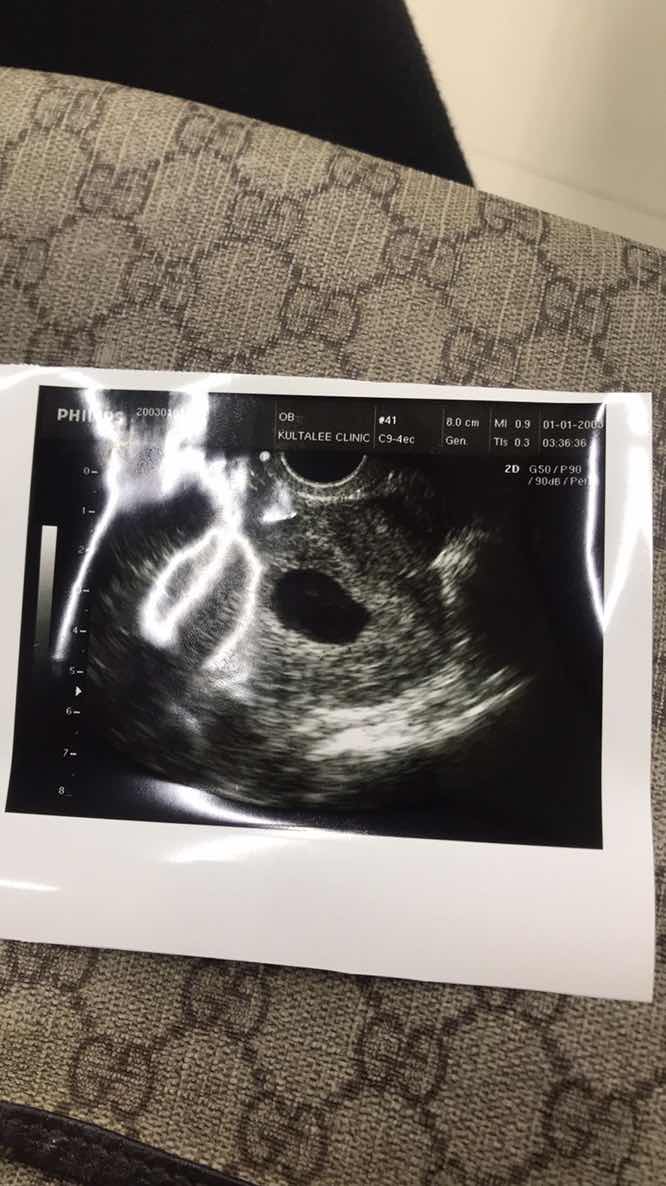

8week 4day วันนี้ไปซาวด์ผ่านหน้าท้อง คุณหมอบอกว่าไม่เจอหัวใจเด็ก คาดว่าจะเป็นท้องลม หมอนัดอีกทีสัปดาห์หน้า เครียดจังเลยค่ะ เครียดมาก เพราะหมอบอกถ้าสัปดาห์หน้ายังไม่เจอจะต้องยุติการตั้งครรภ์ คุณแม่บ้านไหนมีอาการแบบนี้บ้างคะ

สู้ๆค่ะแม่ อย่าคิดมากค่ะ ท้องลมคือ ไม่มีตัวเด็กค่ะ ไม่ต้องเสียใจ เกิดจากการปฏิสนธิไม่สำเร็จค่ะ บ้านนี้เคยท้องลมเหมือนกันค่ะ ภาพนี้ตอน 8สัปดาห์ ไม่มีตัวเด็กเลยค่ะ หาไม่เจอ พอ10ส่ปดาห์ เลือดเริ่มออกมาทีละนิดๆ จน 12 สัปดาห์ไปตรวจอีกที ถุงครรภ์ฝ่อค่ะ

ภาพตอน 12 สัปดาห์ค่ะ หลังจากนั้นก็ยุติการตั้งครรภ์ ของเราแท้งสมบูรณ์ค่ะ ไม่ได้ขูด มันหลุดออกมาเองเลยค่ะ หลังจากที่หลุดไปประมาณ 6 เดือน น้องก็มาเลยค่ะ ตอนนี้ใกล้คลอดแล้วจ้า เป็นกำลังใจให้นะคะ 🥰🥰